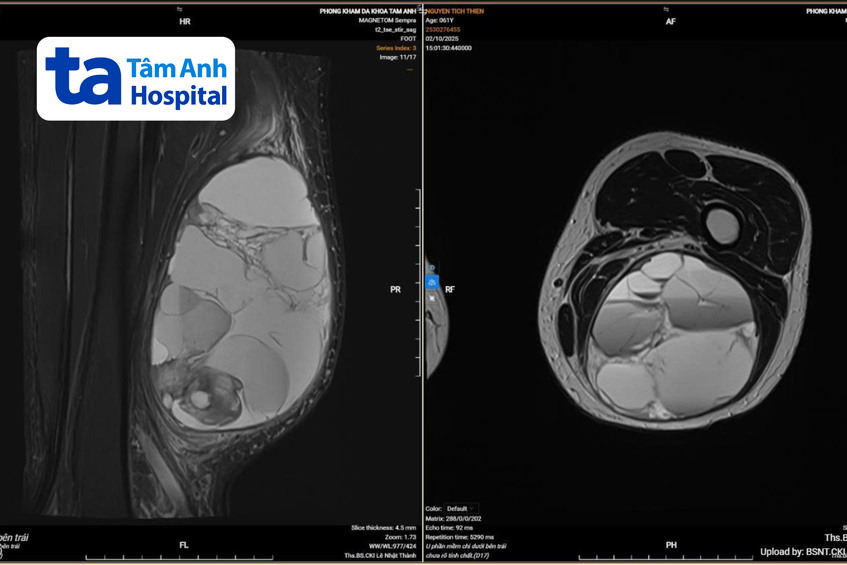

Ông Thành đang bị suy tim và mắc kèm nhiều bệnh nền như tăng huyết áp, rung nhĩ, rối loạn lipid máu. Do đó, ông được điều trị kiểm soát bệnh tim mạch trước trong hai tuần, sau đó mổ sinh thiết, làm các dấu ấn miễn dịch khối u để xác định chính xác ung thư mô liên kết cơ trơn, làm cơ sở để điều trị lâu dài. Kết quả chụp CT toàn thân của ông Thành cho thấy ung thư chưa di căn về mặt đại thể. Hình ảnh MRI tại chỗ cho thấy khối u rất lớn, chèn ép, xô đẩy các cấu trúc giải phẫu lân cận.